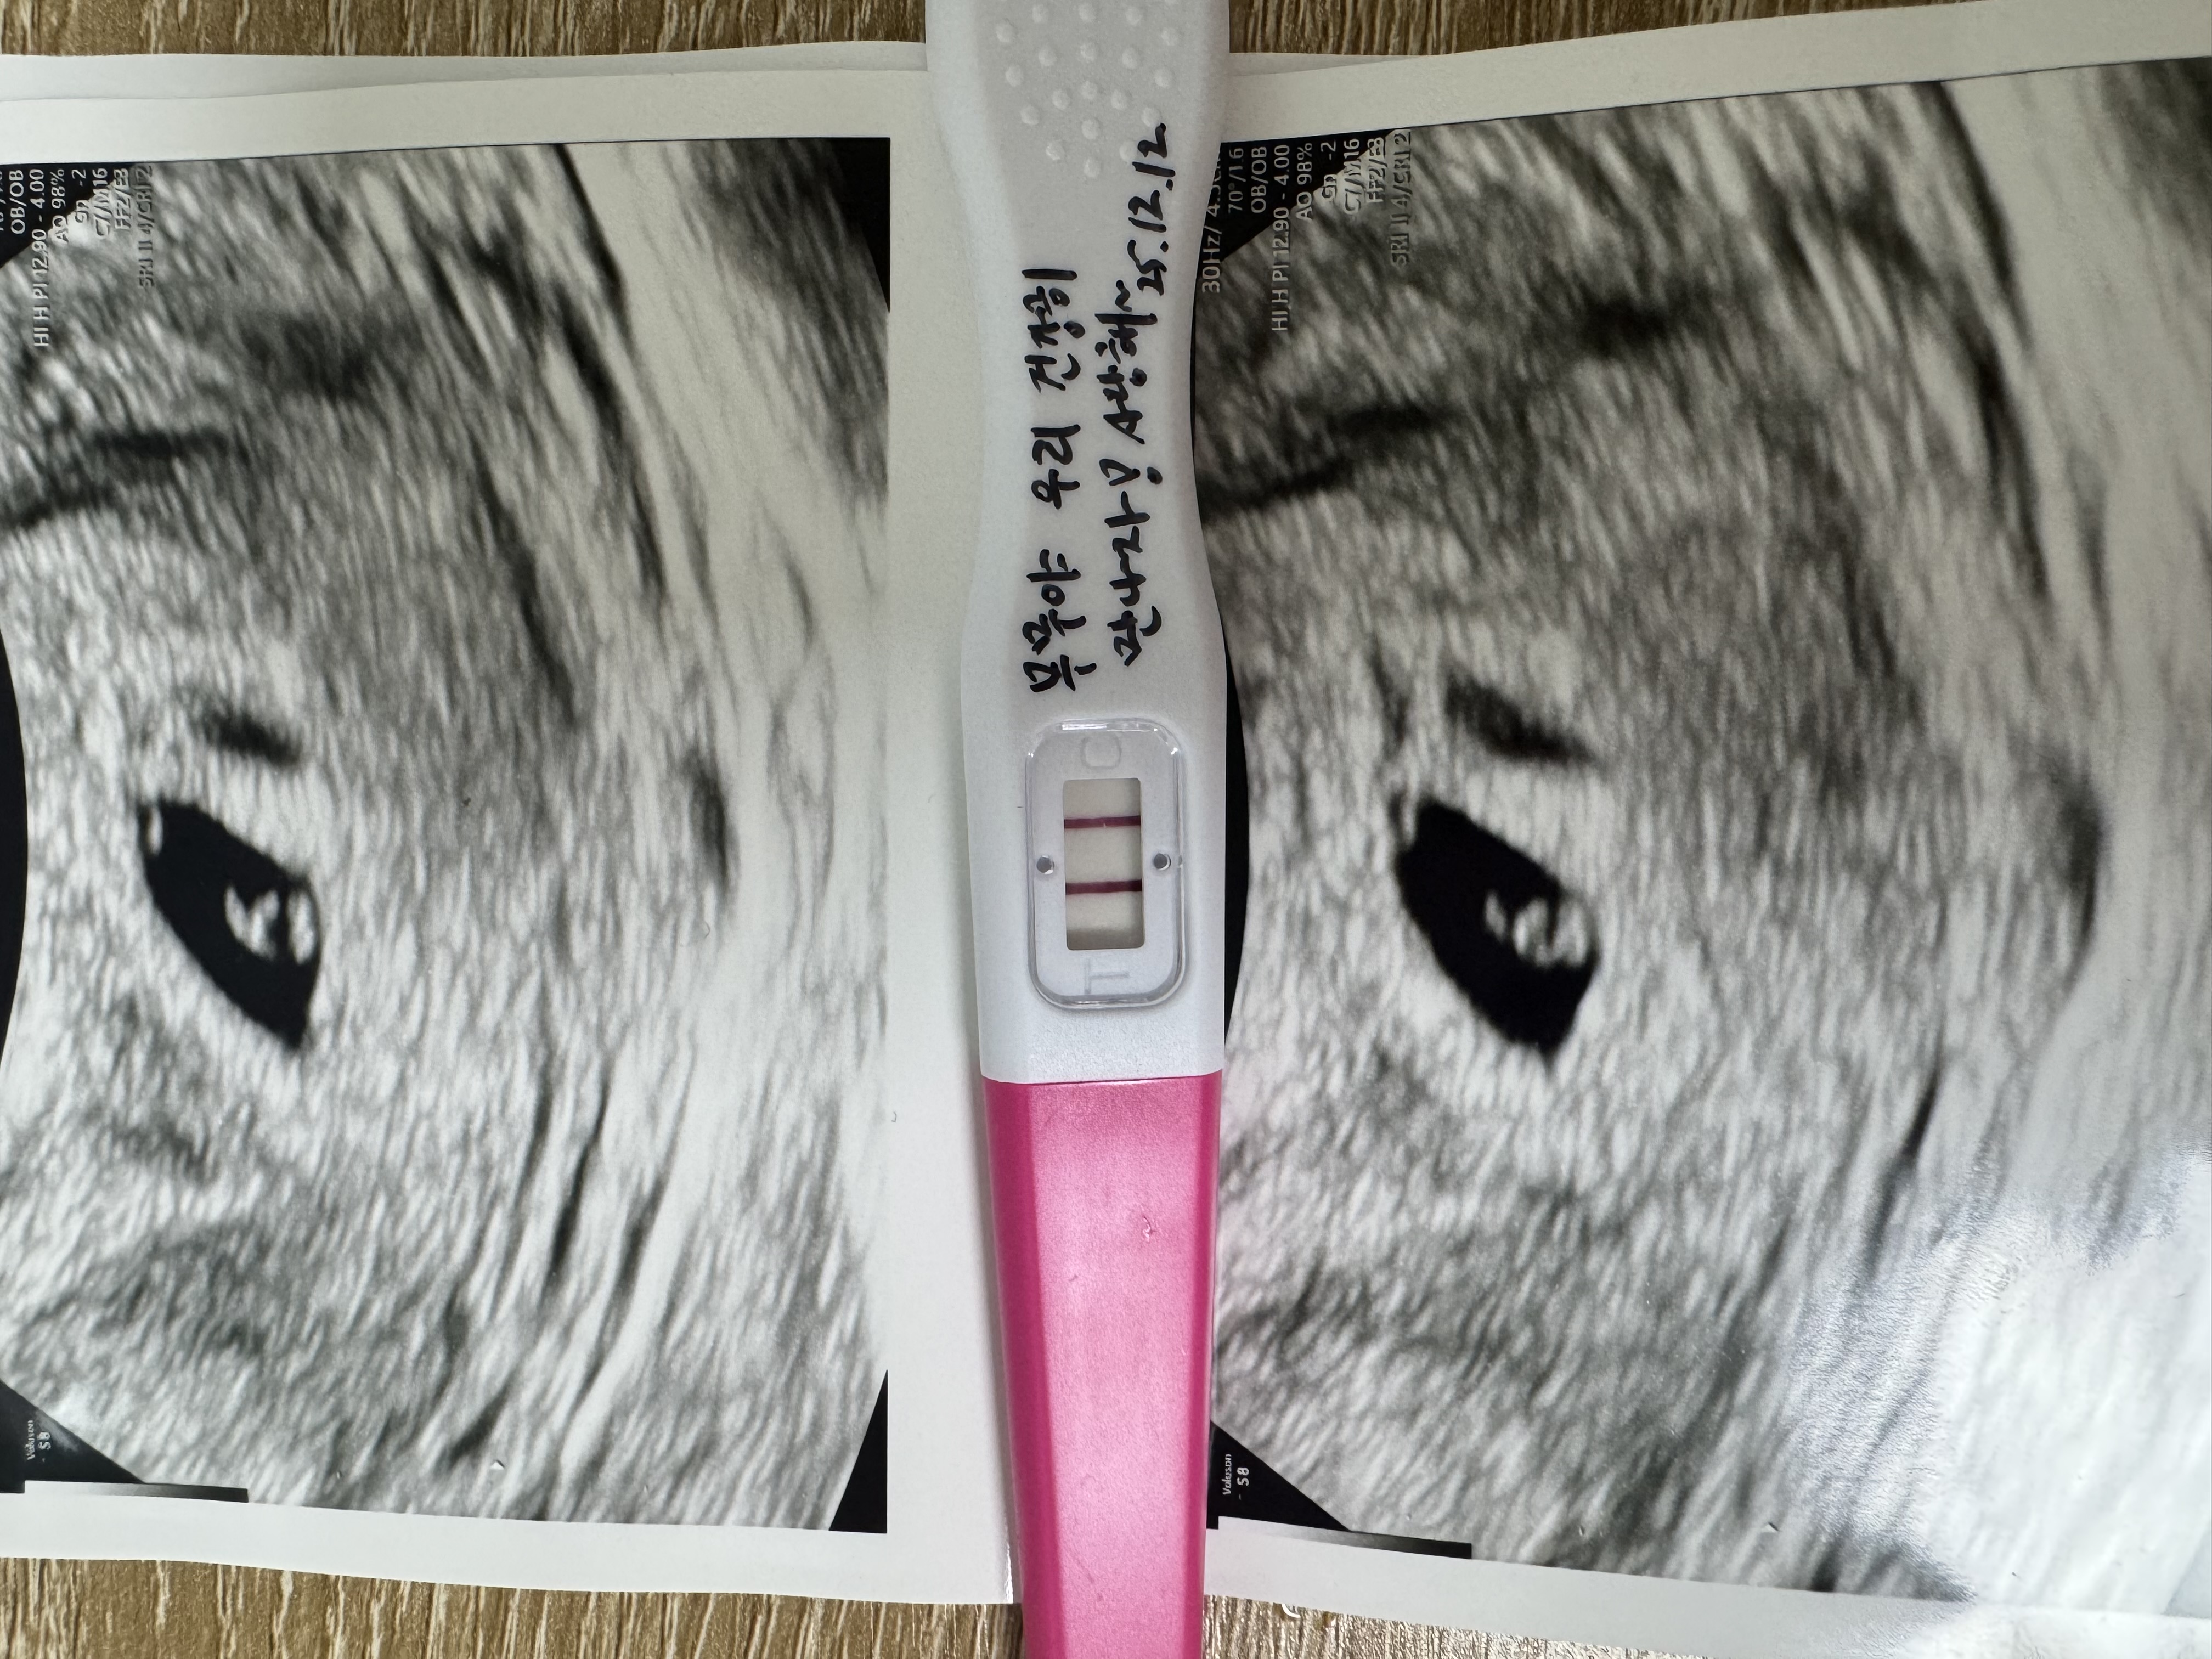

기대하지 않았던 두 줄, 그리고 끝까지 이어진 믿음 - 희망나눔